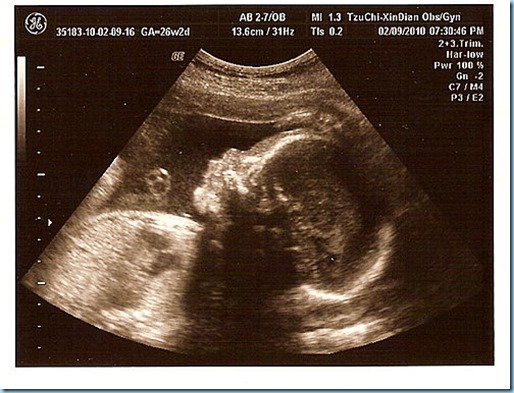

2010/02/10

目前是26週...我的體重53.2Kg...

小小辰1022公克........

今天是要檢查妊娠糖尿症....

先喝50g葡萄糖+250cc水....等1個小時抽血....

門診費+自費$242元

P.S起初喝到50cc時....還覺得蠻好喝的....

但喝到100cc的時候....就有點不行了...哈~~~

1個小時候抽血...這次是抽2根試管...另一個要驗B肝...